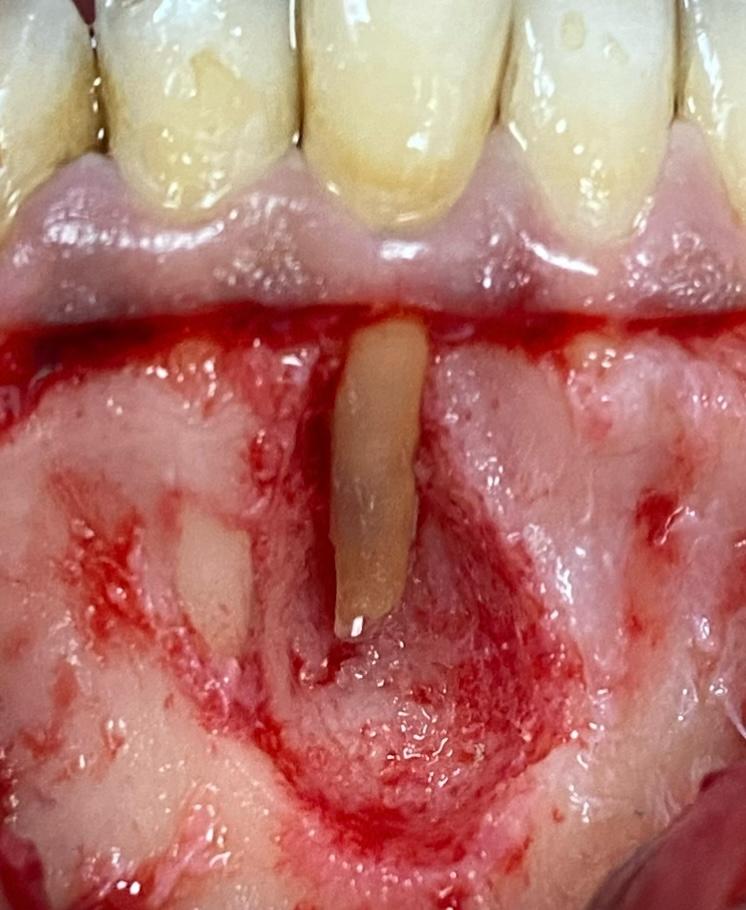

Se le realiza un TAC donde se observa una imagen radio lúcida de 11,3 mm de ancho y 8,5 mm de largo Esta imagen es compatible con un quiste odontogenico del 41 posiblemente causado por un fracaso endodontico. La imagen radiográfica afecta también al 42 pero dicho diente está vital. Se realiza un colgajo para hacer la quistectomía y apiceptomía del 41. Se regenera con hueso autólogo: xenoinjerto en una proporción 70:30 y membrana de colágeno STD de media reabsorción.

Los procesos quísticos de gran tamaño, pueden ser resueltos mediante la extracción del diente y extirpación del quiste. En este caso el hueso remanente hubiera sido insuficiente para posteriormente poner un implante, asique se decide hacer quistectomía y regeneración ósea guiada del defecto óseo